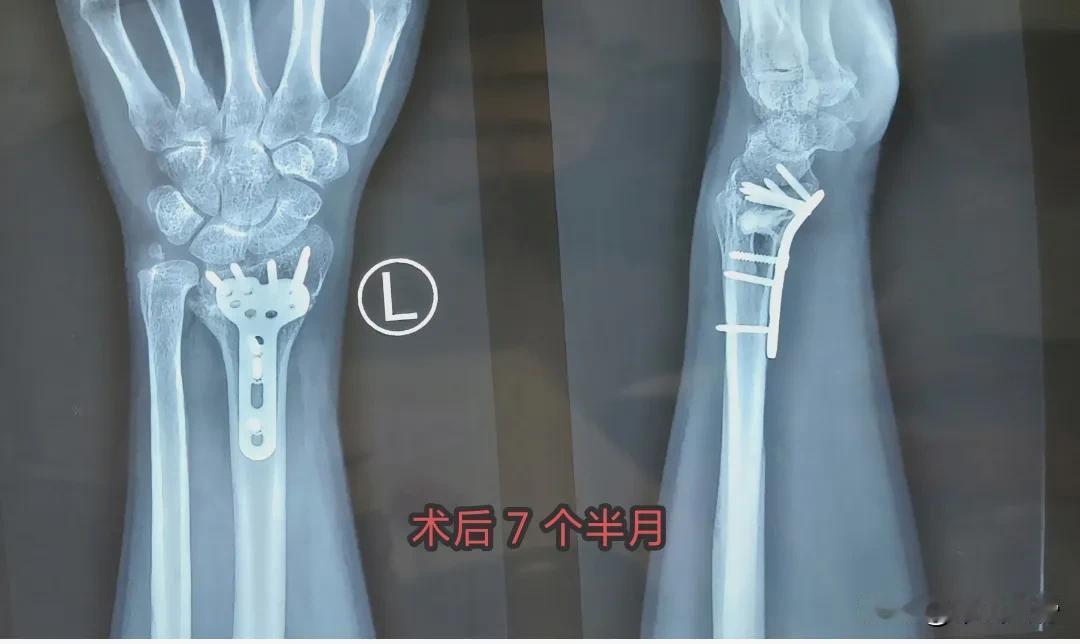

麻烦大夫给看看,这个恢复的咋样?左桡骨远端

桡骨远端骨折以及掌骨骨折练好握拳很关键,这是一组很好的手指握拳锻炼方法教程,根据

桡骨远端骨折以及掌骨骨折中药熏洗治疗方案: 艾叶、川芎、苏木、白芷、伸筋草、透骨